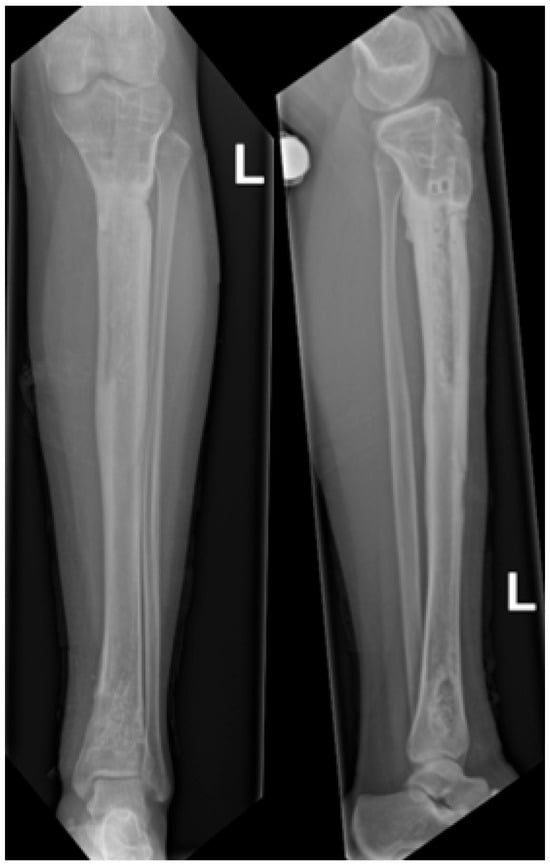

At two-year follow-up, the patient showed marked improvement compared to preoperative status, reporting only occasional mild pain related to weather changes on the Visual Analog Scale 1/10, with no functional limitations. Clinical examination revealed a normal gait, healed and non-tender surgical scars, full range of motion of the knee and ankle, and preserved motor function. Residual hypoesthesia over the lateral lower leg was present without functional impact. Based on clinical assessment and patient-reported function, a retrospective Musculoskeletal Tumor Society score was estimated at 28/30. The patient reported normal quality of life and unrestricted participation in daily activities. No limb-length discrepancy or coronal/sagittal deformity was observed. Postoperative MRI showed no recurrence of the tumor (Figure 9).

Figure 9.

Postoperative MRI following hardware removal, T1 TIRM sequence, coronal plane, showing no residual lesion, no abnormal signal, and preserved tibial architecture at the previous lesion site, consistent with absence of recurrence.